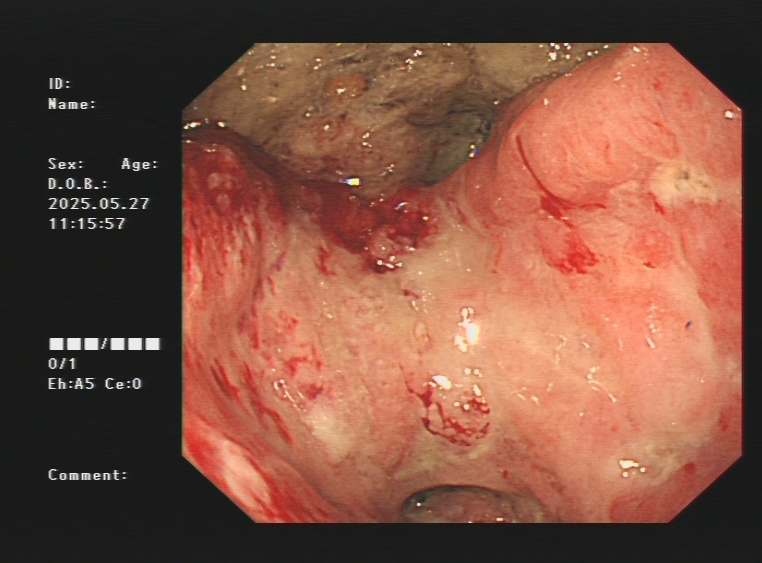

1.上消化道出血常见原因:消化性溃疡(胃溃疡、十二指肠溃疡)、食管炎、急性糜烂出血性胃炎、上消化道肿瘤(食管癌、胃癌)、剧烈呕吐造成的食管贲门黏膜撕裂伤、肝硬化引起的食管胃底静脉曲张。以下是一些常见的上消化道出血内镜图片:

食管癌、胃癌出血